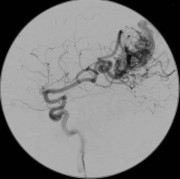

Dat kan met een MRI-scan (Magnetic Resonance Imaging), maar de beste manier om een AVM te ontdekken is een angiografie. Dit is een soort röntgenfoto, maar dan voor je aders. Die zijn op een gewone röntgenfoto niet te zien. Bij een angiografie wordt er een speciale vloeistof in je aders gespoten, waardoor deze wel zichtbaar worden. Dat gebeurt via een katheter, een slangetje dat via de lies of arm wordt ingebracht.